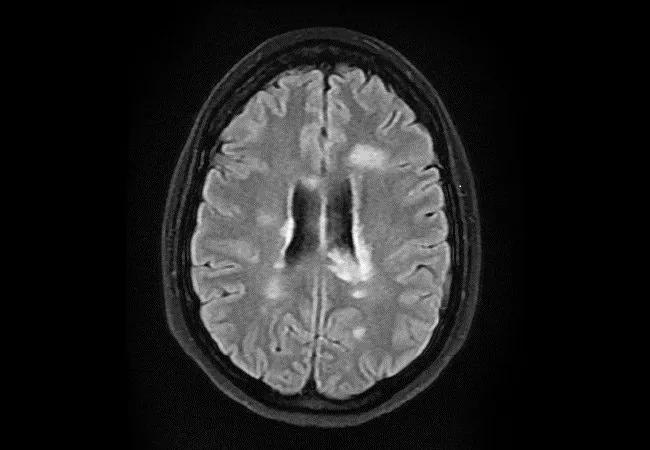

17-NEU-4135-Hersh-Ontaneda-MS-MRI-650×450

MRI as treatment target

In a separate study, we used an observational design to investigate MRI stability as a treatment target in MS.6 A treat-to-target approach to MS management has gained increased acceptance, with “no evidence of disease activity” (NEDA) — in which patients are free of relapses, disability progression and MRI activity — as the preferred target.7 While NEDA seems a sensible goal, there is limited evidence that it leads to better long-term outcomes.

Our study utilized the Knowledge Program, a Cleveland Clinic-developed database used to electronically collect patient- and clinician-reported outcomes longitudinally.8 We identified 417 patients who had activity on their MRIs and then determined if they remained on the same DMT or were switched to an alternative therapy. After PS matching, we compared clinical and radiologic outcomes after 18 months in 78 switchers and 91 nonswitchers. No significant differences were observed between the groups.

Our study did not show a short-term benefit of switching treatment, but it is possible that efficacy differences are apparent only after longer follow-up. It is also worth considering the possibility that zero tolerance of new MRI lesions, which is required to achieve NEDA, may be too stringent a goal. To reach such a target, most patients will require escalation to treatments with more safety concerns,9 so it will be important to justify that risk by demonstrating that achieving NEDA leads to better long-term outcomes.